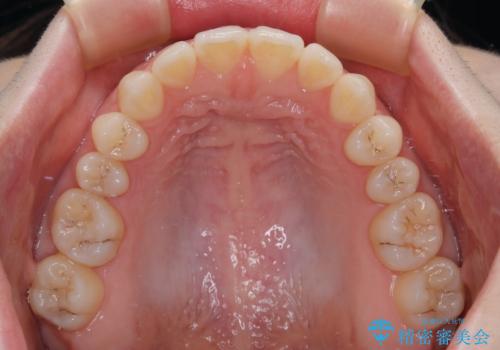

すきっ歯をインビザラインできれいな歯並びに改善

- 1年5ヶ月

隙間や叢生の程度はそれほど著しいものではなかったので、インビザラインでもワイヤー矯正でも対応可能でしたが、極力目立たない装置を希望されたため、インビザラインにて矯正治療を行うこととしました。

すきっ歯の原因は色々ありますが、嚥下や発音時の舌突出癖が大きな原因となることがあります。

こちらの患者様も強い突出癖があったため、舌のトレーニング指導を行いました。